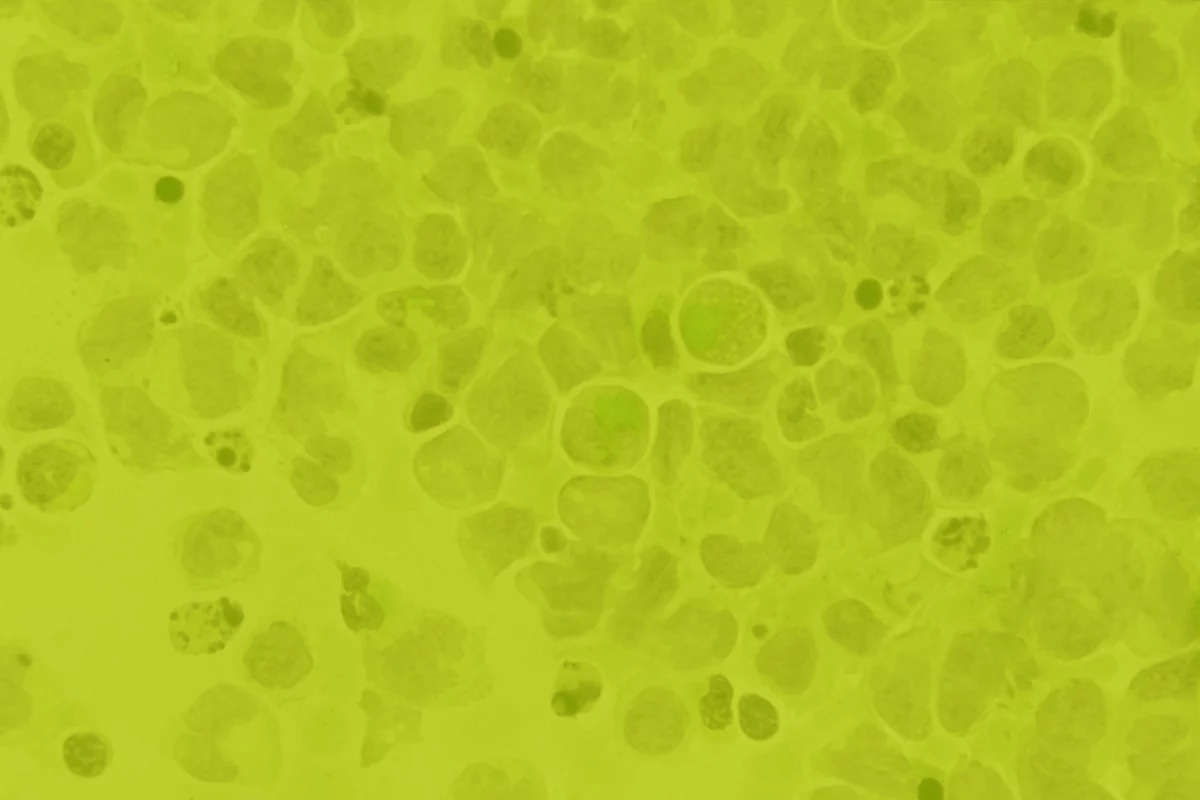

Al convertirte en benefactor, contribuyes al apoyo de los pacientes que están camino al trasplante de células madre.

Por cada peso que los benefactores donan a NMDP México®, se aportan 90 centavos a los pacientes, todo lo relacionado con el proceso del trasplante de células madre y a la búsqueda de su potencial donador. Conoce la distribución de las aportaciones que recibimos:

42%

Financiar gastos de pacientes en camino al trasplante

21%

Adquirir elementos necesarios para nuestros eventos de registro

19%

Analizar información genética de donadores y estudios correspondientes

18%

Encontrar la compatibilidad genética entre pacientes y donadores